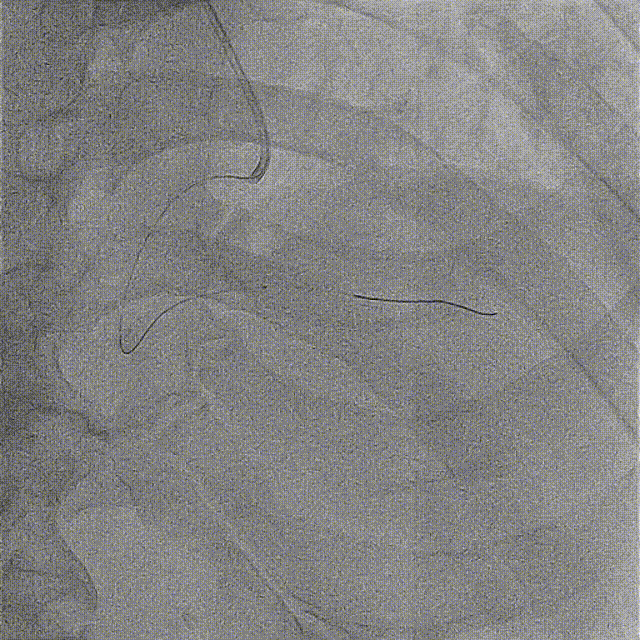

预扩后右冠远端显影,远段及PD开口处可见血栓,抽吸出约2cm长血栓1条。

抽吸一次后PD血流好转,仍见血栓影,PL未见显影,再次抽吸。

于PD抽吸后血流消失,PL显影,送导丝到PL远端。

反复尝试PL、PD抽吸及球囊扩张。

先后于3条分支球囊低压扩张,及冠脉内注入欣维宁。